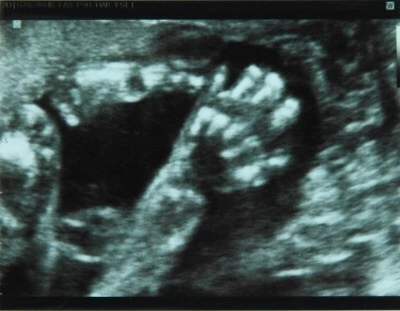

하지만 온누리는 내가 조금의 입덧도 하지 않게 하고, 몸이 붓지도 않게 하고, 살이 트지도 않게 해 주며 엄마가 힘들지 않도록, 조용히 세상에 나올 준비를 하는 착한 아기다.

조금씩 부풀어 오르는 배

그리고 조금씩 불편해지는 몸

아가야

내 몸을 쓰렴,